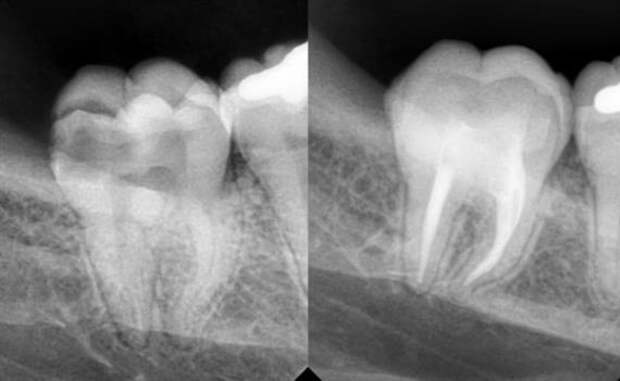

Рентгеновские снимки кариеса корня зуба

Раздел: Визуальные уроки